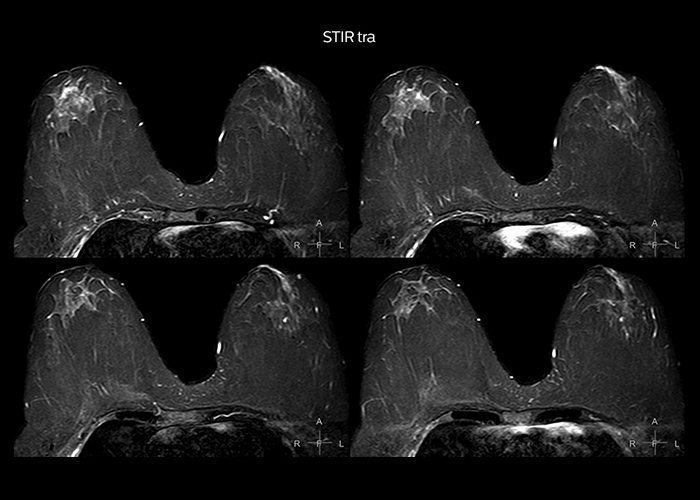

“On average, we scan about 80 patients per day, but on some days we scan well over 100 patients. The scanner is in use 7 days per week, operated 20 hours per day on week days and 8 hours per day in the weekend,” Mr. Tuna says. “To avoid coil changes we plan examinations of similar anatomies back to back, such as head and spine. Multiva helps us here a lot because coils don’t need to be changed frequently. Moreover, thanks to parallel imaging technology and 16-channel HeadSpineTorso and 8-channel MSK coils we are able to achieve excellent image quality. In this way Multiva helped us to increase both image quality and productivity.” “Neurological cases, such as brain and spine imaging, represent the largest share in our MR scanning, followed by musculoskeletal cases. In general, we use simple and basic imaging protocols. But occasionally, we use advanced techniques for problematic cases if necessary.

“Since we have Multiva, we have improved our workflow, because it has been so easy for our operators to learn and use Multiva. Our operators notice that the coils are lightweight and coils don’t need to be changed frequently. The user interface is easy to use. Features like this help us to scan a high number of patients. For instance, the musculoskeletal coils can be used interchangeably, and due to the user-friendly interface, the number of mistakes such as, for example, correct coil element selection has decreased significantly, because the system does it automatically by itself.” “Most important, Multiva satisfies our clinical imaging needs very well,” says Mr. Tuna. “Many features of Multiva have become similar to the Ingenia system. Even in more complex imaging such as abdominal and cardiac, the image quality and performance of Multiva is better than we expected. General surgeons and physicians from our hospital’s internal medicine department prefer to refer to us because of this.”